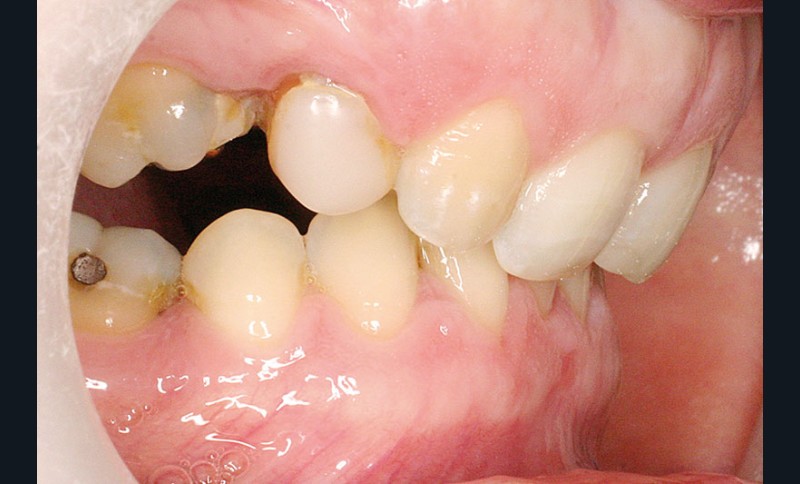

La patiente, âgée de 30 ans, présente des agénésies multiples : 12, 22, 14, 15, 24, 25, 35 et 45 (fig. 1 à 3).

On note une forte supraclusion incisive (fig. 7 à 9).